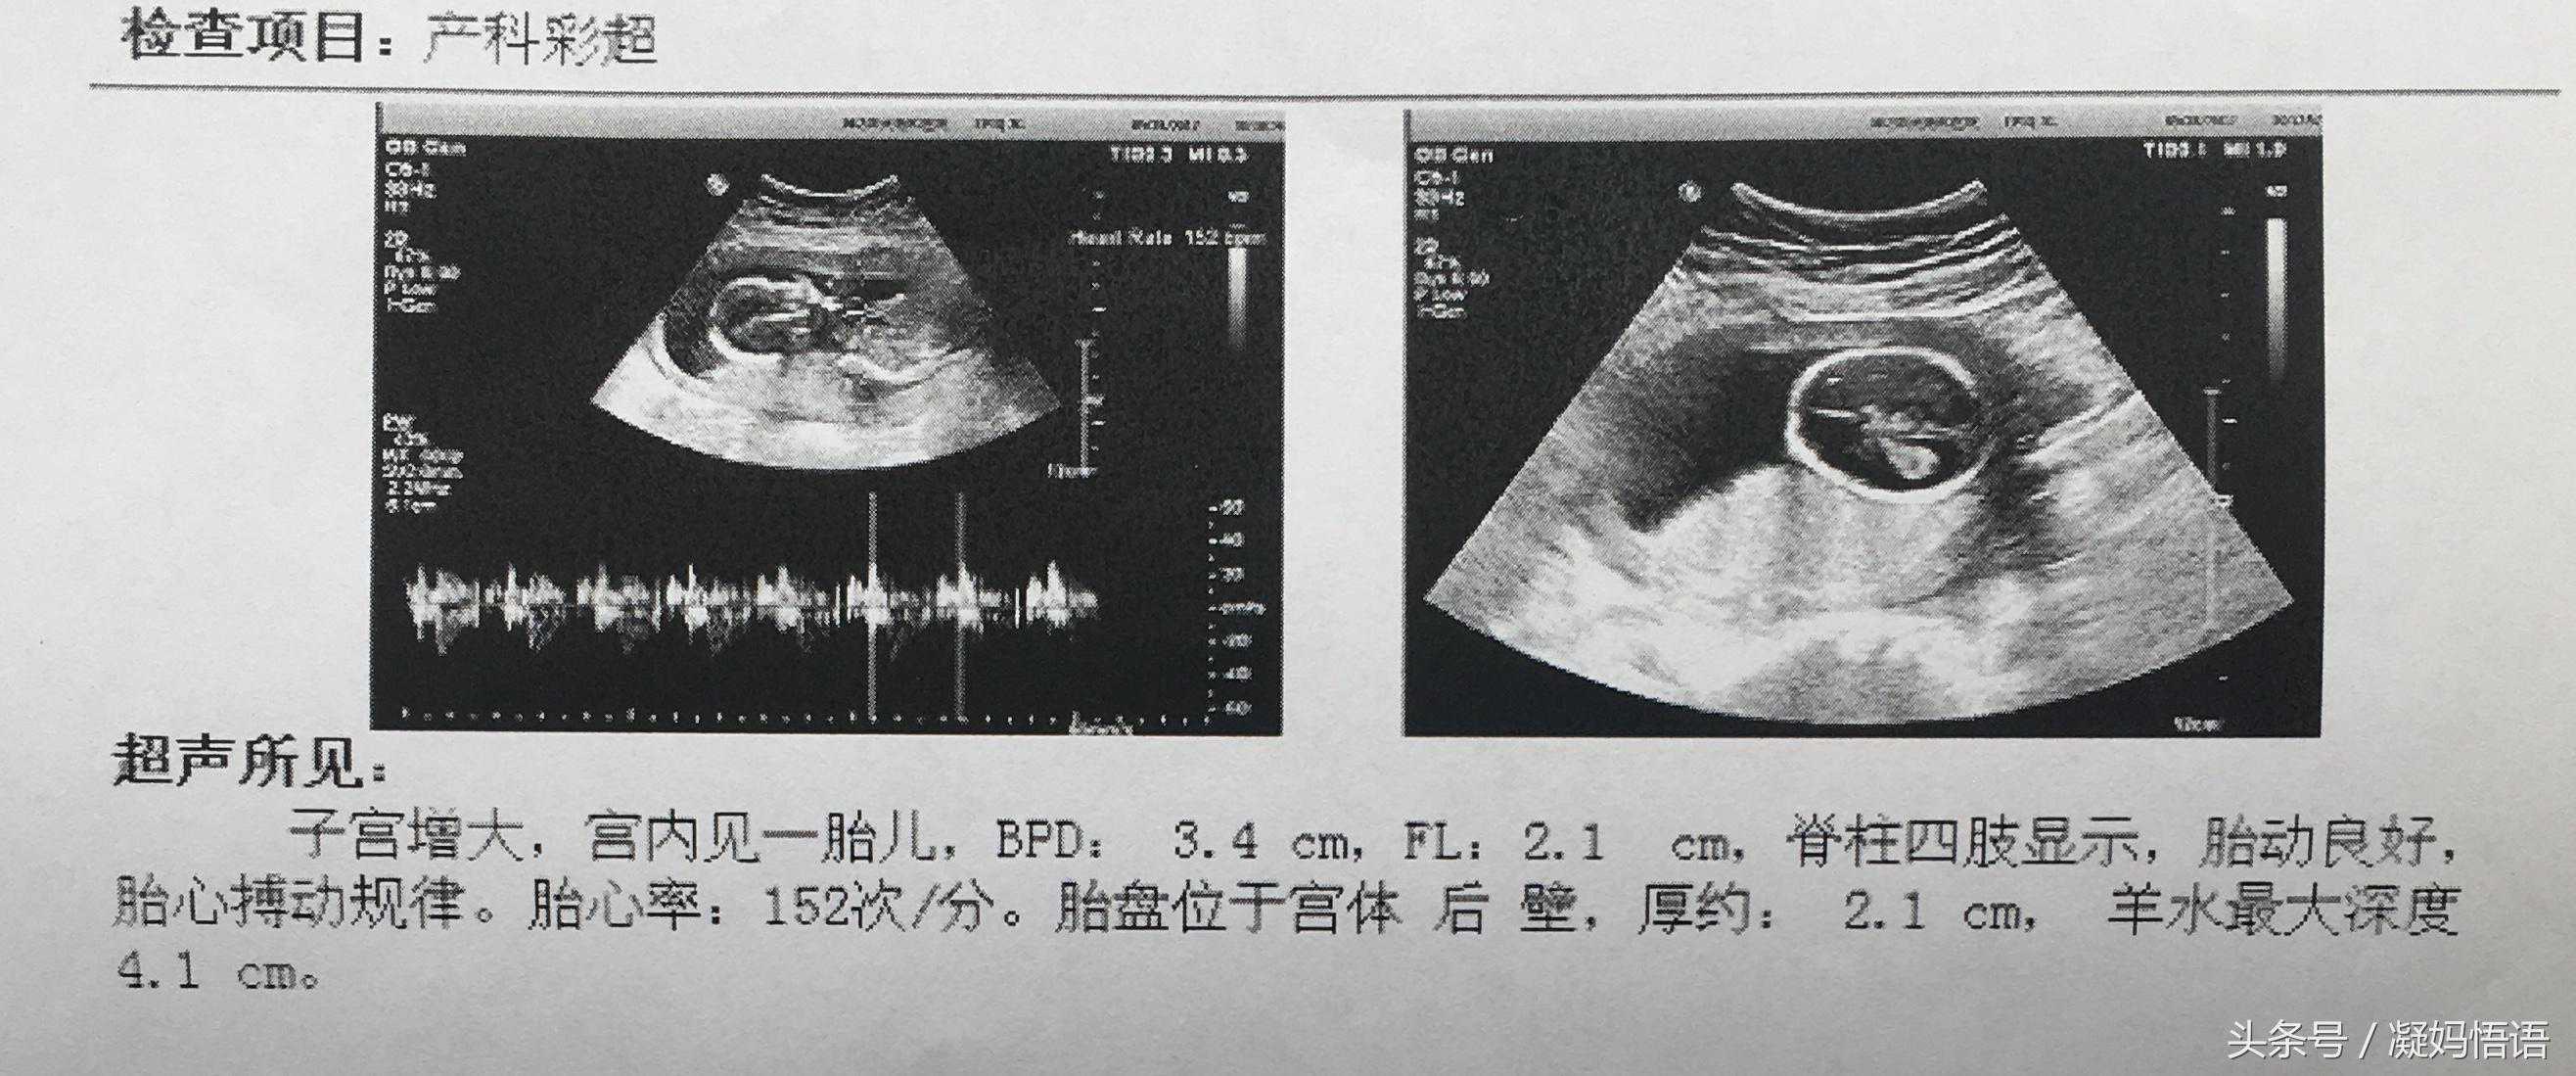

一、第一次彩超是在第7周,确认是否宫内受孕,不是宫外孕。

有朋友说胎心率高于140是女孩,我们家可是男孩,不准。

三、第三次彩超是在第17周,例行检查。

再次证明胎心率高于140是女孩是不准确的。

这时的双顶径是3.4cm,股骨长是2.1cm,3.4-2.1=1.3,此时月份小,估计不准确。